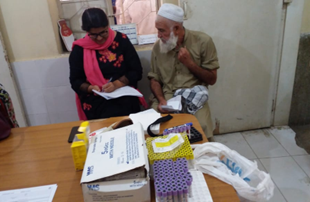

Glycemic control in type-2 diabetes mellitus patients through non-surgical periodontal therapy – a randomized controlled trial was conducted over a period of three years (2019 – 2021). This project involved the screening phase where adult population were screened for type-2 diabetes having periodontal problems followed by a trial phase where the selected individuals were randomized in two tests and a control group. The test groups were intervened with the scaling with root planning covered by an antibiotic, and other alone with scaling and root planning. It was learnt that non-surgical periodontal therapy in the form of scaling and root planning helps achieve glycemic control as indicated by HbA1c levels after three and six months.

This project was a joint venture by the Department of Community Dentistry, Periodontology, National Institute of Diabetes & Endocrinology (NICE) and Dow Diagnostic Lab (DDRL) under the umbrella of Dow University of Health Sciences Karachi. This was the only project from Low-Middle-Income Countries (LMIC) particularly from Pakistan that was cited by the Cochrane Oral Health Group – UK. The NICE- UK guidelines for diabase management were updated after informed by the Cochrane Review. For detailed findings of this project click on this video message or follow link on our official social media: https://www.facebook.com/share/v/1BzhDpGTVv/